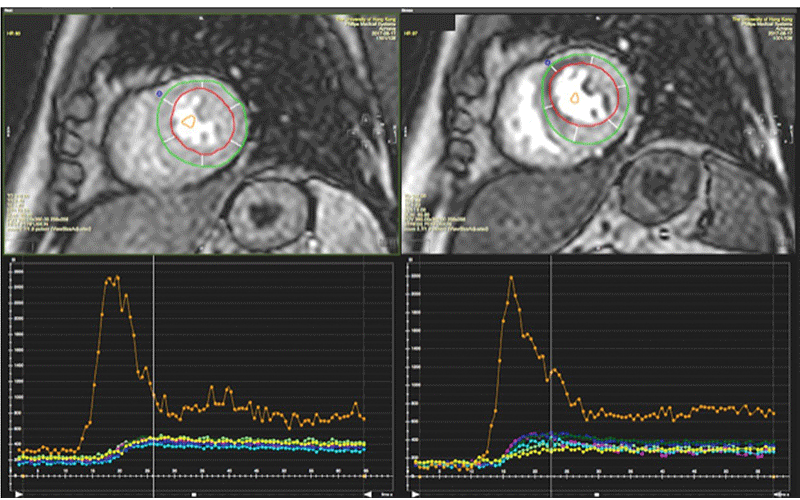

“About 20% of asymptomatic patients with type 2 diabetes have silent ischemia,” said lead author Ming-Yen Ng, BMedSci, BMBS, clinical assistant professor, Department of Diagnostic Radiology, HKU. “Secondly, about 50% of patients have coronary microvascular dysfunction as seen on cardiac MR.”

Coronary microvascular dysfunction is becoming increasingly recognized as a significant risk for earlier death and myocardial infarcts, but currently there are no effective therapies. “Drugs that potentially improve coronary microvascular function could be studied using stress cardiac MR,” Dr. Ng said.

To assess for perfusion defects resulting from microvascular disease, which can be difficult to differentiate from obstructive CAD, the team analyzed the global myocardial perfusion reserve index (MPRI) in the patient cohort and determined that the low median MPRI value (1.38) indicated that half of the patients likely had microvascular disease.